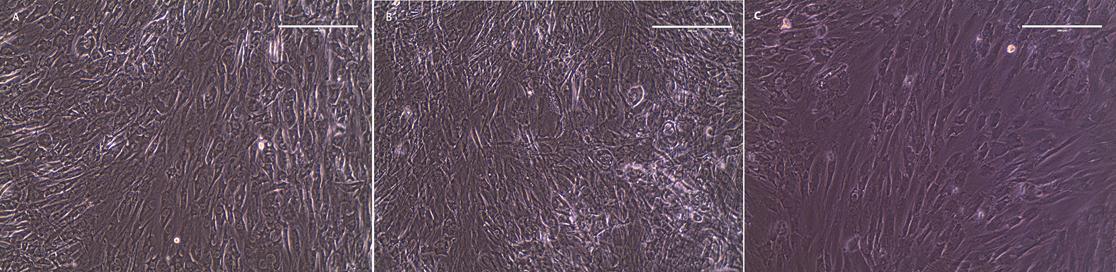

Light microscopy demonstrated that cultures induced to differentiate into adipogenic and osteogenic cell types showed morphological changes after 2 weeks in culture (Figure 1). After 28 days in culture, induced cells showed positive staining for lipid after adipogenic culture (Figure 2A) and mineral deposits after osteogenic culture (Figure 2B) while their respective negative controls showed no staining.

Figure 1.Phase contrast microscopy of rabbit ASC cultured under adipogenic (A), osteogenic (B), and control (C) conditions for 14 days on 2-dimensional plastic culture plates. Both experimental conditions have lost the spindle shape and linear arrangement still present in the control. Magnification 20x; scale bar 200m.